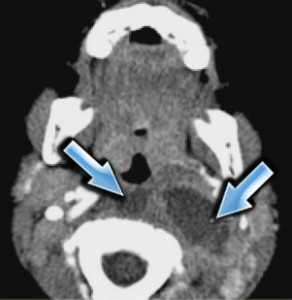

Ретрофарингеальное пространство заполнено тонкой прослойкой жировой ткани. В этом пространстве могут быть заглоточные абсцессы с характерной клиникой: температурой ознобом и нарушением глотания. Инфекция попадает при фарингитах, из соседних лимфатических узлов и, как исключение, при травме инородными телами ( рыбья кость и т.д.). Заглоточные абсцессы опасны отеком и обструкцией дыхательных путей. Поэтому они часто требуют неотложного хирургического вмешательства.

КТ. Ретрофарингеальные абсцессы.